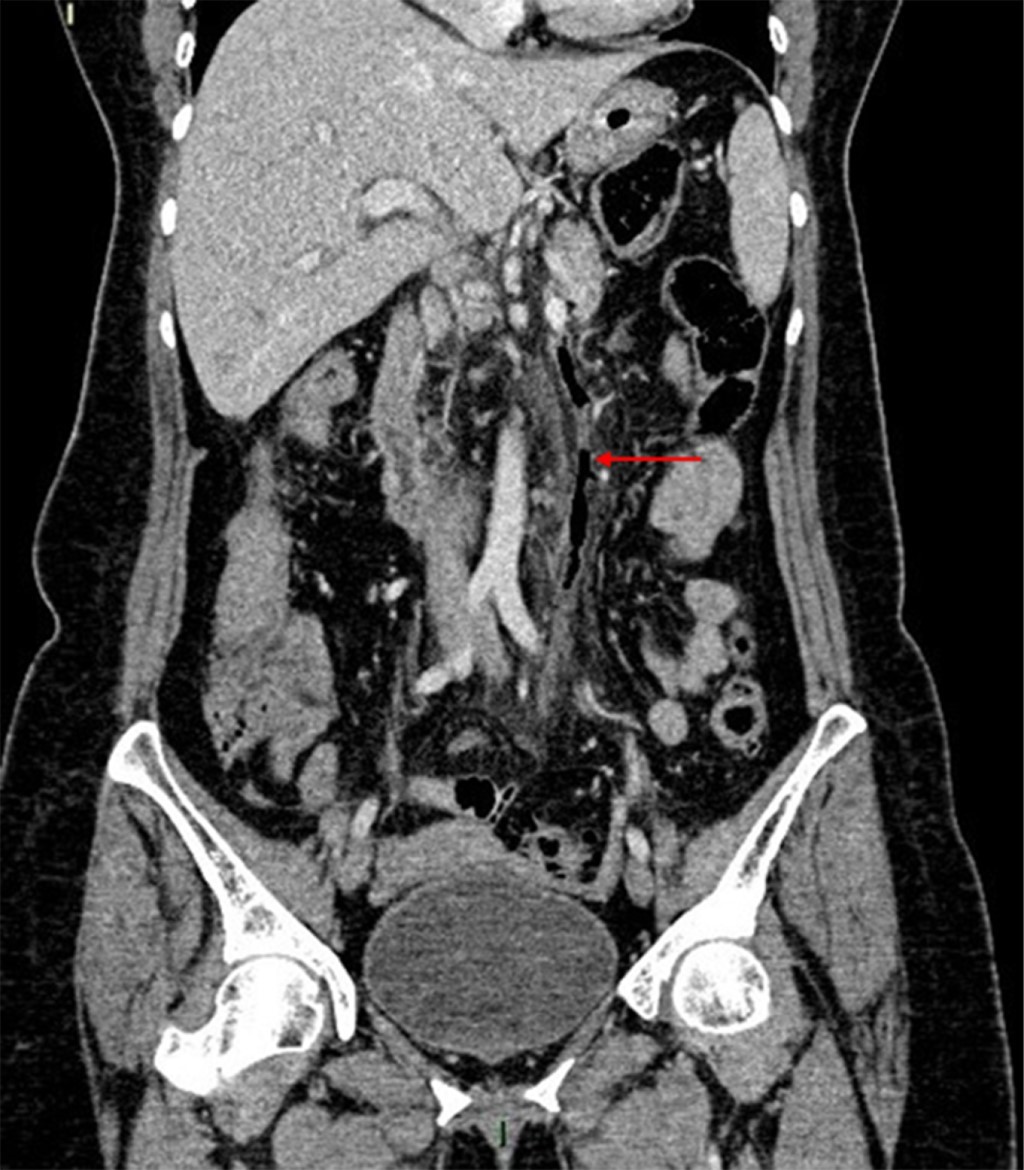

Introduction: pylephlebitis, also known as ascending septic thrombophlebitis, is characterized by embolic occlusion of the portal-venous system and its branches, secondary to intra-abdominal infection. Clinical case: a 63-year-old female came for abdominal pain, as well as a fever of 39.4 °C. They presented leukocytosis, increased C-reactive protein, procalcitonin, and liver function tests. A tomography was performed, observing air thrombus in the inferior mesenteric vein and thrombus in the left portal vein, with data of diverticulitis. Conclusions: pylephlebitis is a rare and severe complication; the radiologist must identify it to establish the appropriate medical treatment.

Figure 1